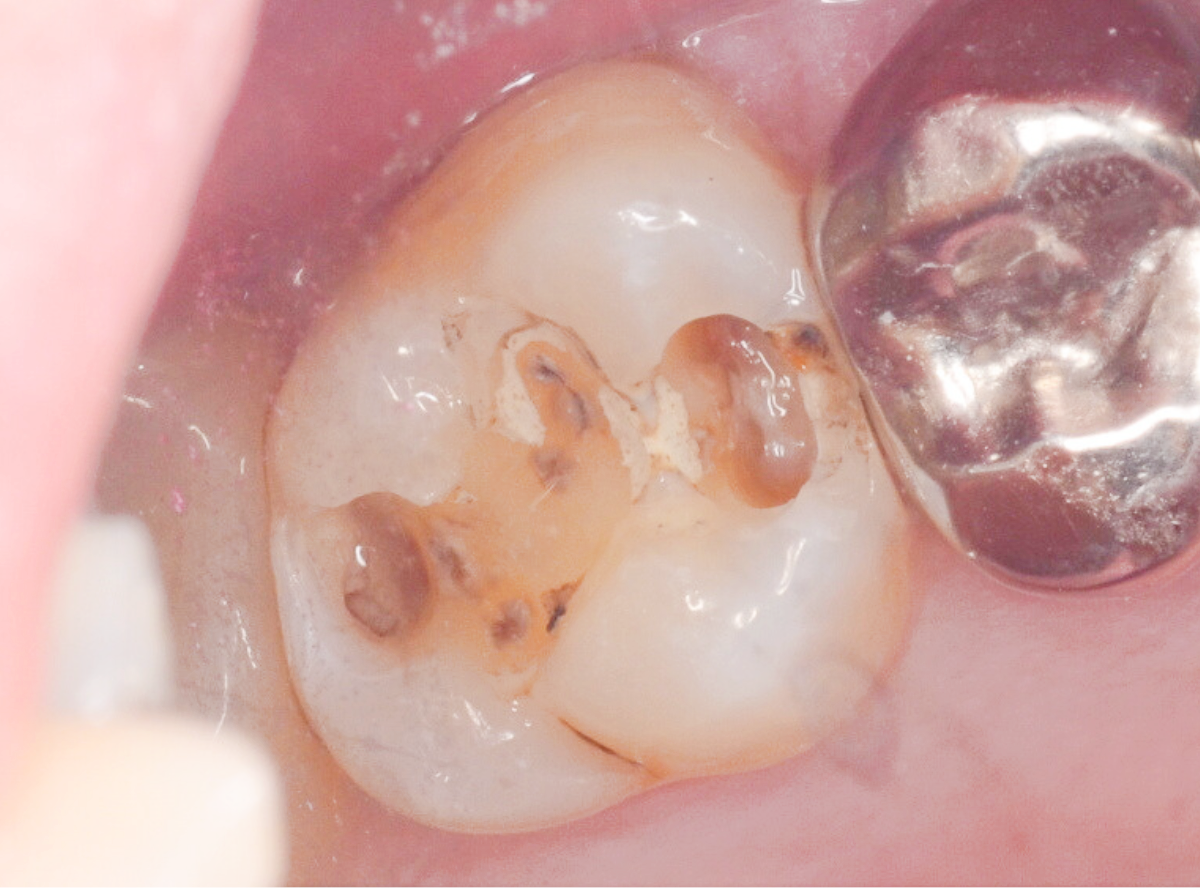

写真は、虫歯治療をしている途中の写真です。どこに虫歯があるかわかりますか?

赤く染まった部分が虫歯です。

そして、虫歯を取り切った写真を見るとかなり大きな虫歯であった事がわかります。

虫歯治療を行う上で一番大切な事は、虫歯に感染した部分をしっかり除去することですが、まずは虫歯の硬さを頼りに、軟らかくなった部分を削っていきます。

「虫歯の部分だけを削るドリル」を使用すれば、それだけでほぼ虫歯は取り除けますが、感染部位を完全に除去できたかわかりづらい時もあります。

このう蝕検知液を併用することで、虫歯を取り残すことなく虫歯治療ができます。

う蝕検知液で細かくチェックする事で、虫歯治療の精度があがります。